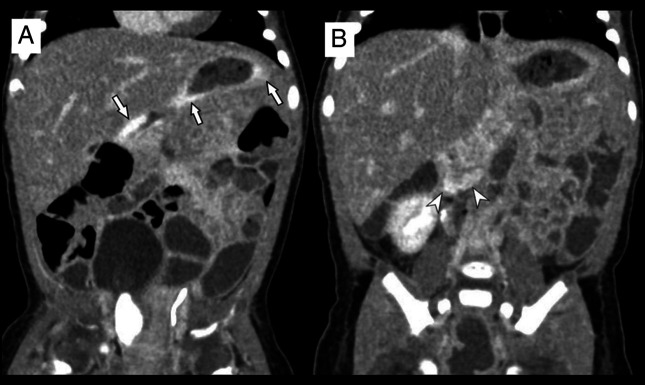

We present the case of a 3-week-old girl with multiple cutaneous vascular lesions, melena, hematemesis, severe anemia (hemoglobin 4.4 g/dL), and thrombocytopenia (72 × 103/µL), with clinical features consistent with multifocal lymphangioendotheliomatosis with thrombocytopenia (MLT). Upper gastrointestinal endoscopy revealed numerous actively bleeding angiomatous lesions, measuring 1-3 mm in diameter. Homeostasis was successfully achieved using argon plasma coagulation (APC). To our knowledge, this is among the few reports describing the effective use of APC in managing life-threatening gastric hemorrhage in an infant with MLT. While gastrointestinal perforation has been previously reported as a complication of endoscopic therapy in this context, our findings suggest that APC may be a viable option for refractory bleeding, provided that surgical support is immediately accessible.